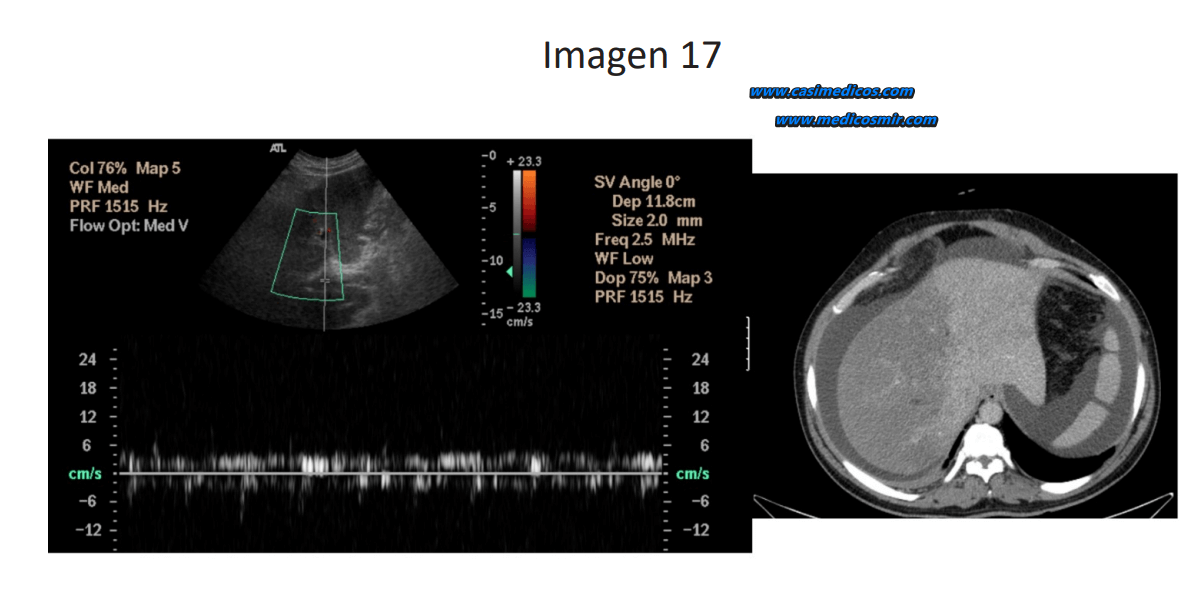

PREGUNTA 17

Pregunta asociada a la imagen 17.

Paciente de 63 años consulta por dolor en flanco derecho, ictericia y aumento del perímetro abdominal. Se realiza ecografía Doppler y TC de hígado como se muestra en la imagen. ¿Cuál de las siguientes es la mejor opción terapéutica?:

1. Colocación de una derivación intrahepática percutánea (TIPS).

2. Anticoagulación oral.

3. Trasplante hepático.

4. Angioplastia percutánea.

Respuesta correcta: 2

Comentario:

En las imágenes se muestra una ecografía Doppler hepática con disminución del flujo portal compatible con trombosis y un TC de abdomen que muestra ascitis y disminución de densidad de gran parte del lóbulo hepático derecho en relación con isquemia hepática. La colocación de TIPS está indicada en pacientes con hipertensión portal grave o trombosis crónica. La anticoagulación oral no es la solución principal en este contexto, el trasplante hepático no es la primera opción ya que el TIPS es una medida menos invasiva y la angioplastia percutánea está indicada en estenosis arteriales o venosas focales.